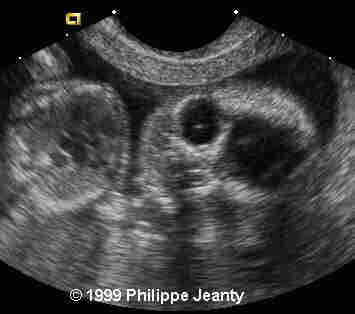

17-year-old primigravida.

This examination is obtained at 18 weeks amenorrhea.

• abnormal cardiac axis

The cardiac axis is a little offset and the interventricular septum incomplete

Very few, however, made the most crucial observation: the great disproportion between the head and abdomen. That disproportion is very typical of triploidy (see the lecture on aneuploidy for another example) and I know of no other conditions where such a big difference exist without a concomitant intracranial anomaly such as hydrocephaly, or teratomas… Of course, one of you will come up with a great differential diagnosis and then we will learn even more !